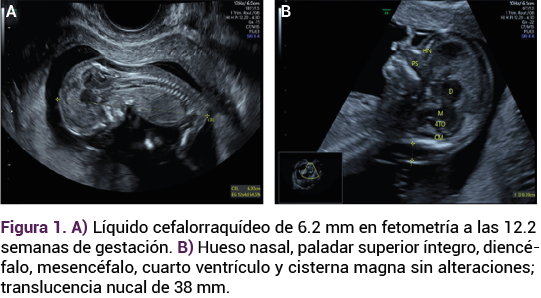

Paciente de 32 años, con antecedente de dos embarazos y una cesárea, indicada por macrosomía fetal, el actual en curso de las 13.3 semanas, por fecha de la última menstruación, con dos consultas de control prenatal, consumo de multivitamínicos, sin infecciones urinarias y vaginales. Sin recuerdo de problemas patológicos. El ultrasonido del primer trimestre reportó: feto único vivo, con frecuencia cardiaca de 163 lpm, con movimientos, placenta anterior corporal, inserción central del cordón umbilical, bolsillo mayor de líquido amniótico de 3.43 cm, longitud craneocaudal (LCC) de 6.20 mm para 12.2 semanas de gestación; translucencia nucal de 39 mm (Figura 1). La ecografía Doppler: IP de ductus venoso de 1.23, IP de arterias uterina derecha e izquierda 0.81 y 1.20, respectivamente. Anatomía fetal, situs solitus, burbuja gástrica, riñones y vejiga sin alteraciones demostrables lo mismo que la anatomía cardiaca.

Figura 1.